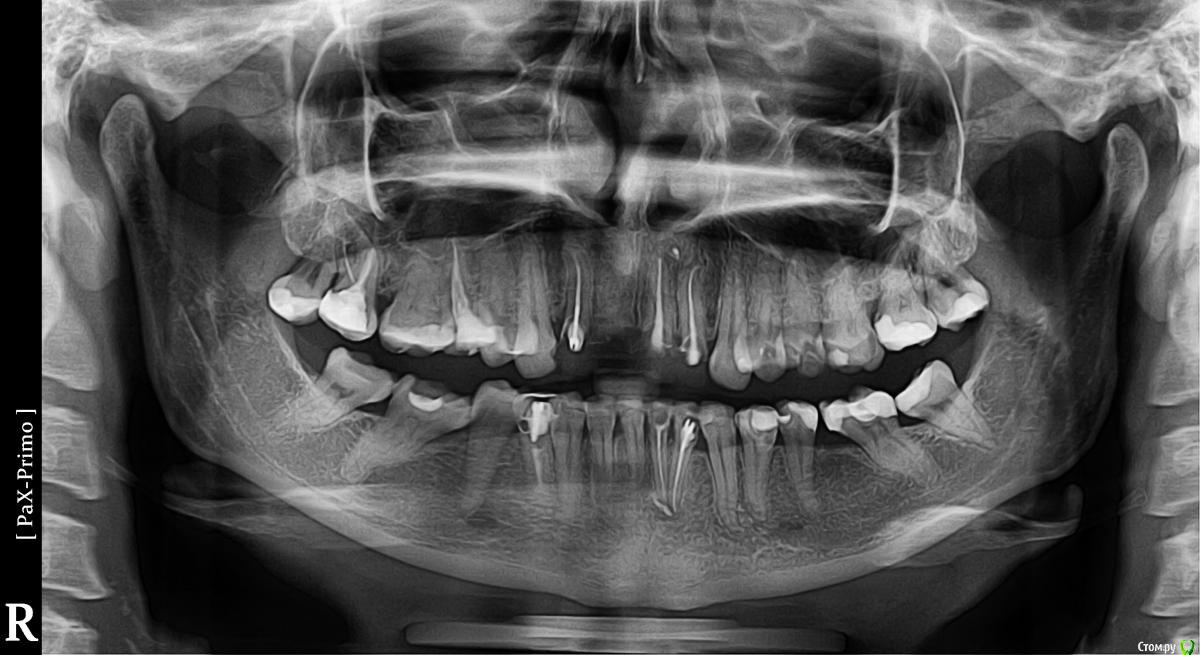

Koloss Опубликовано 18 сентября, 2015 Поделиться Опубликовано 18 сентября, 2015 Здравствуйте, уважаемые доктора! Ставлю коронку на 4-й нижний зуб справа. Этот зуб лечился и депульпировался около 7 лет назад, все это время был под пломбой. Врач решил не перепломбировать канал, не менять штифт, говорит: штифт стоит крепко (хоть и коротковат) , зуб не беспокоит, и на снимках не видно корня - лучше его не трогать раз не беспокоит. Как Вы считаете как лучше поступить с этим зубом и почему нижние правые 1-4 корни зубов на панорамных снимках такие размытые? Нижние зубы от клыка до клыка зашинированы после брекетов. Спасибо Ссылка на комментарий

IvanK Опубликовано 18 сентября, 2015 Поделиться Опубликовано 18 сентября, 2015 Убрать штифт, оценить визуально и рентгенологически пломбировку корневого канала, вкладка и коронка 1 Ссылка на комментарий

Гарриевич Опубликовано 18 сентября, 2015 Поделиться Опубликовано 18 сентября, 2015 По хорошему штифт нужно убирать, перелечивать или нет в зависимости от состоятельность корневой пломбы Ссылка на комментарий

molchanoff Опубликовано 18 сентября, 2015 Поделиться Опубликовано 18 сентября, 2015 и анкер со 2го слева нуна выгнать Ссылка на комментарий

molchanoff Опубликовано 19 сентября, 2015 Поделиться Опубликовано 19 сентября, 2015 и анкер со 2го слева нуна выгнать А вместо анкера в двойке, что должно быть? И чем чревато оставить как есть?1 свш и коронка2 а сами че думаете? Ссылка на комментарий